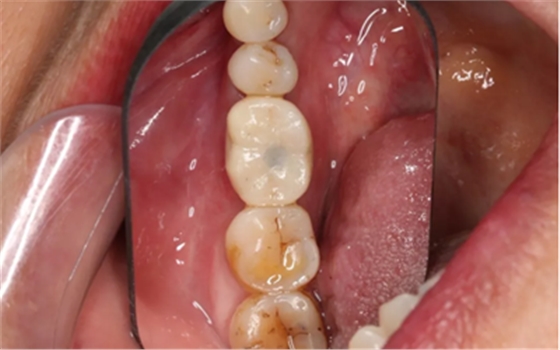

常规制作全瓷冠,试戴合适,粘接固位。

(摄于2018年6月13日)

常规制作全瓷冠,试戴合适。